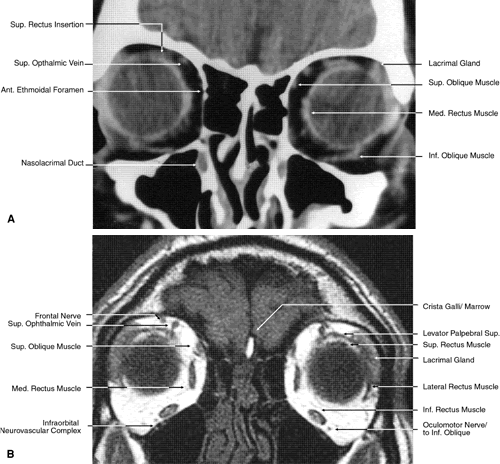

The globe is shown in Figure 12. The orbit and periorbital structures are shown in Figures 13 through 16, and the optic canal is shown in Figures 17 through 26. The cavernous sinus and optic chiasm are shown in Figures 27 and 28, and the posterior visual pathway and cranial nerves are shown in Figures 29 through 33.

Fig. 18. Coronal images through midglobe. A. Computed tomography scan. B. T1-weighted magnetic resonance imaging.

Fig. 19. Coronal images through midorbit posterior to the globe. A. Computed tomography scan.B. T1-weighted magnetic resonance imaging.